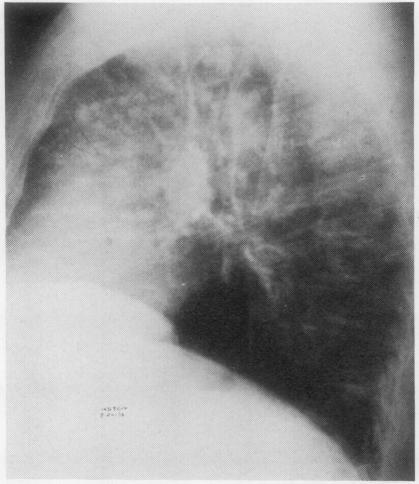

A case of multiple nodular pulmonary amyloidosis in a 54-year-old Caucasian man is presented. Discrete symptomless radiodensities had developed in this patient's lungs within a period of three years, leading to a suspicion of a neoplastic process. The amyloid nature of these nodules was demonstrated by biopsy. In this case, as in others previously reported, there was no evidence of systemic disease, and immunoglobulins were normal. Local factors probably play an important part in the pathogenesis of this disease. This entity is to be distinguished from the diffuse type of pulmonary amyloidosis, which has a far graver prognosis. Diffuse alveolar septal amyloidosis is usually associated with primary systemic amyloidosis or multiple myeloma and leads rapidly to respiratory distress.